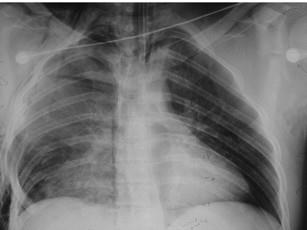

问题 男,20岁,因车祸压伤右前胸引起胸痛、呼吸困难,前胸有一块胸壁软化区,并见反常呼吸运动,X线片如图。急救措施应首先选择 ( )

选项 A、内固定 B、给氧 C、输液、输血 D、加压包扎固定 E、镇静止痛

答案 D